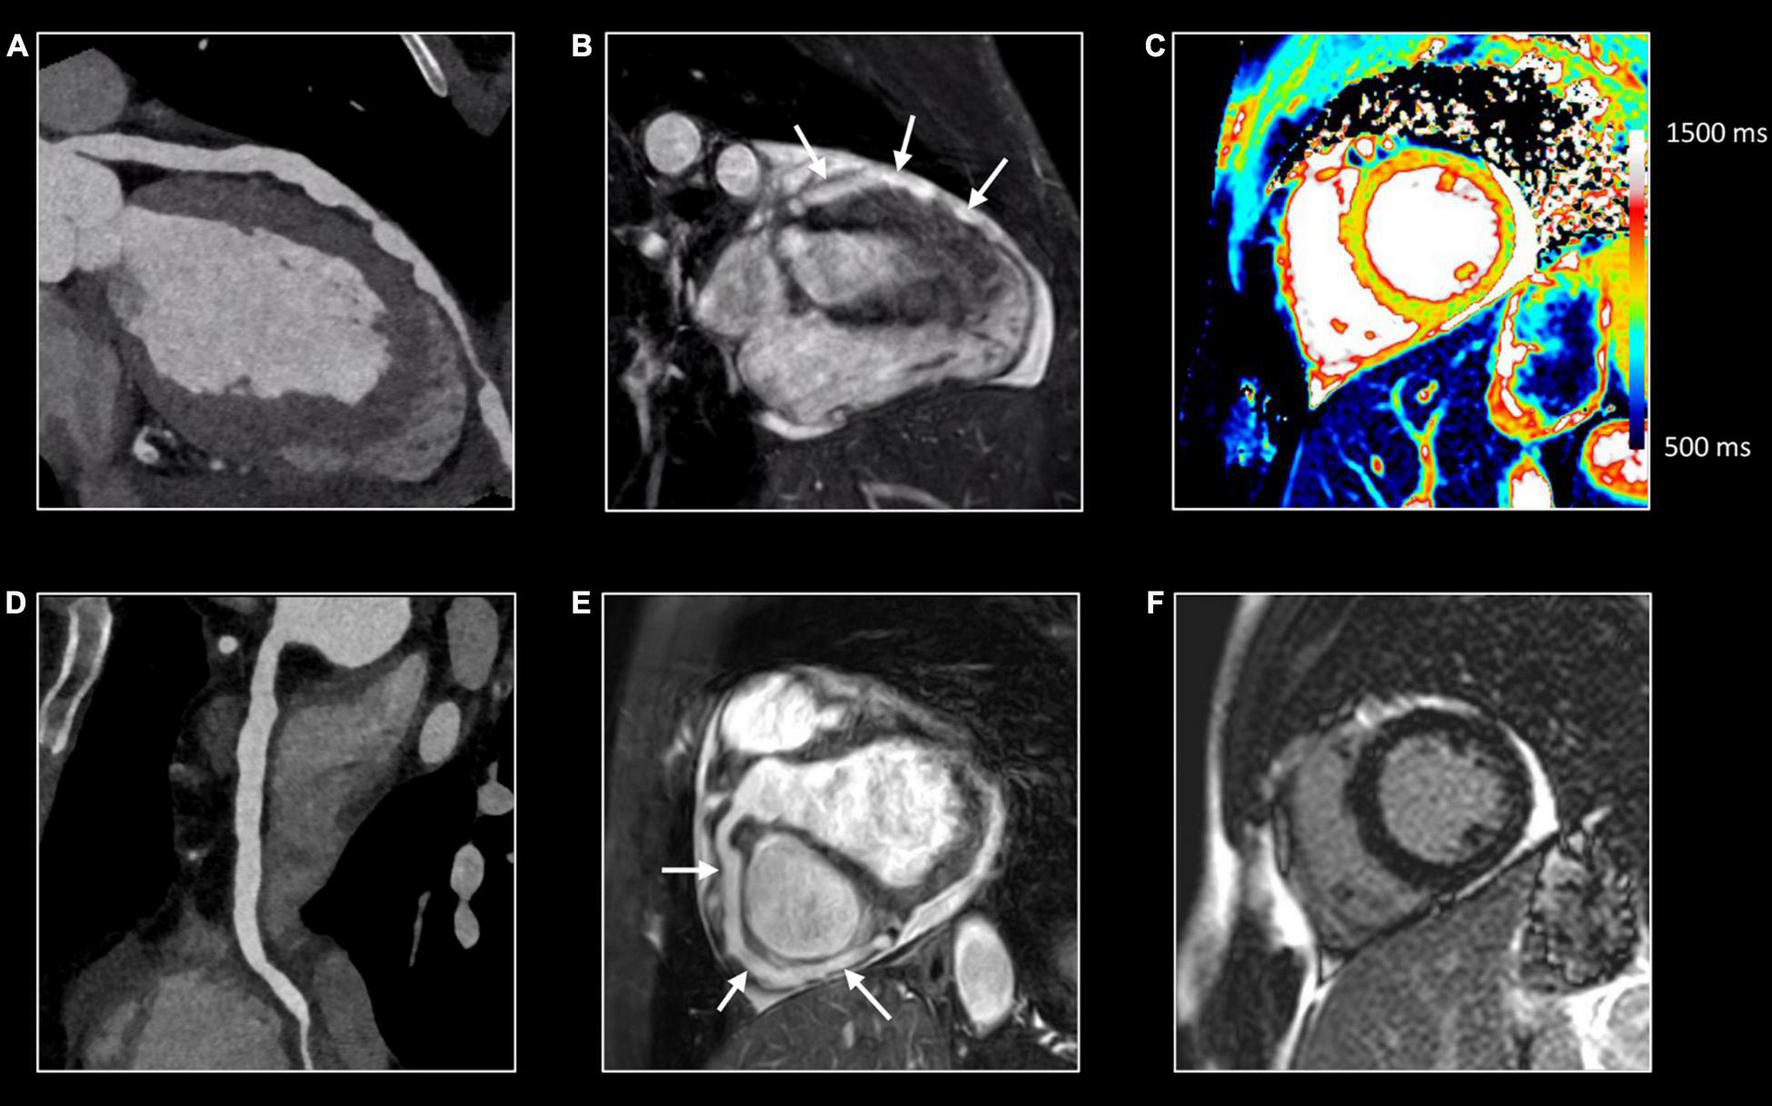

FIGURE 5

Comprehensive imaging in coronaritis. Twenty-seven-year-old man with systemic vasculitis, likely adult-onset Kawasaki disease), admitted with non-STEMI. Computed tomography (CT) (A,D) and CMR (B,E) of the coronary arteries show irregular aneurysmatic dilation (up to 8 mm) of the coronary arteries with on the left anterior descending (LAD) coronary artery several skip areas (focal pseudostenoses). Although the CMR was requested because of clinical suspicion of non-STEMI, CMR revealed no myocardial edema (normal T1/T2 mapping) (C) nor abnormalities at LGE imaging (F) suggestive of myocardial necrosis and/or fibrosis. Further investigation showed a normal caliber of the thoraco-abdominal aorta. However, aneurysms were found on several middle-sized abdominal arteries, including the celiac trunk, common hepatic artery, superior and inferior mesenteric artery and both renal arteries.